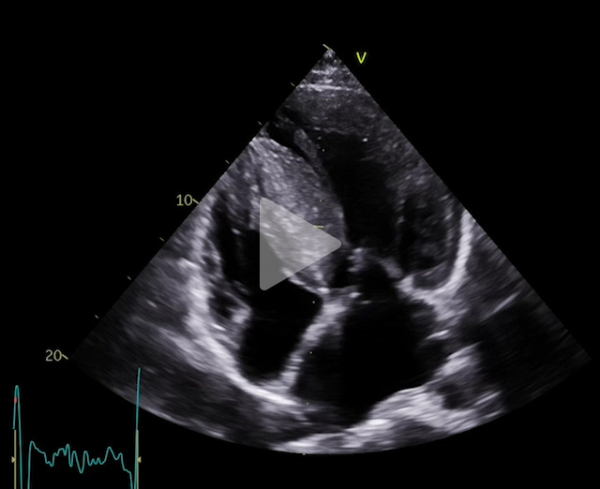

Voici son échocardiographie

Vidéo 1 : échocardiographie 2D en incidence parasternale grand axe

Vidéo 2 : échocardiographie 2D en incidence parasternale grand axe avec doppler couleur

Vidéo 3 : échocardiographie 2D en incidence parasternale grand axe zoomée sur la valve mitrale

Vidéo 4 : échocardiographie 2D en incidence petit axe centrée sur la valve mitrale

Vidéo 5 : échocardiographie 2D en incidence apicale 4 cavités

Vidéo 6 : échocardiographie 2D en incidence apicale 3 cavités avec zoom sur valve mitrale et chambre de chasse ventriculaire gauche

Figure 2 : flux Doppler continu trans-aortique d’obstruction

Figure 3 : flux Doppler continu trans-mitrale d’IM

Figure 4 : superposition des 2 flux Doppler continu d’obstruction sous aortique et d’IM

- Patient de 40 ans avec une CMH sarcomérique (mutation HTZ MYBPC3) avec épaisseur maximale en antéro-septo-basal à 33mm en IRM, associée à une obstruction sous aortique significative (GD max 77 mm Hg au Valsalva). Découverte d’une insuffisance mitrale (IM) sévère mixte organique sur prolapsus de P2 et fonctionnelle sur un SAM (mouvement systolique antérieur de la valve mitrale)